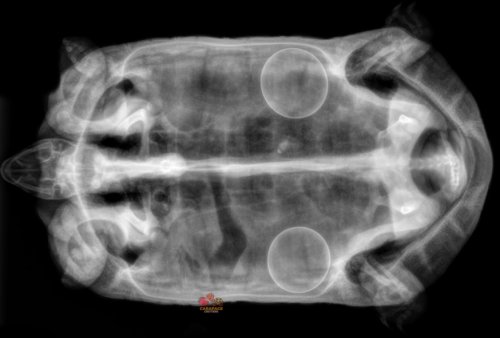

Carousel post from carapacecritters.

December 08, 2025

Taco gave me a bit of a scare recently when she seemed to have issues with egg laying this cycle. Sh...